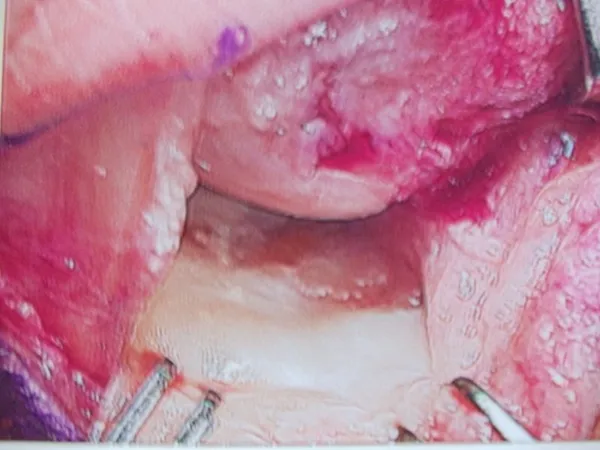

These injuries will most often heal with conservative care but it may take many months before it goes on to complete healing. During the healing process, x-rays will not change, as the bones will not grow back together because of the cartilage that is between them. We can evaluate the healing based on the patient’s pain that they are experiencing while walking and examining them to check for tenderness. Once tenderness and pain are diminished, then an orthotic is made to go in the patient’s shoes or sneakers to unload the metatarsal further and allow the patient to return to sports and activities as desired. In some cases, these injuries do not heal and one or more of the pieces of bone on the ball of the foot needs to be removed. A small incision is placed on the inside of the first metatarsal joint and a piece of the bone is removed. The soft tissue is repaired and immobilization for 3-6 weeks is necessary to allow the area to heal completely. The long-term prognosis is usually excellent.

Intraop Pics of Synchondrosis sesamoid fracture

The fracture can be seen. Due to continued pain, a sesamoidectomy was performed. The bone is unhealthy and was removed.